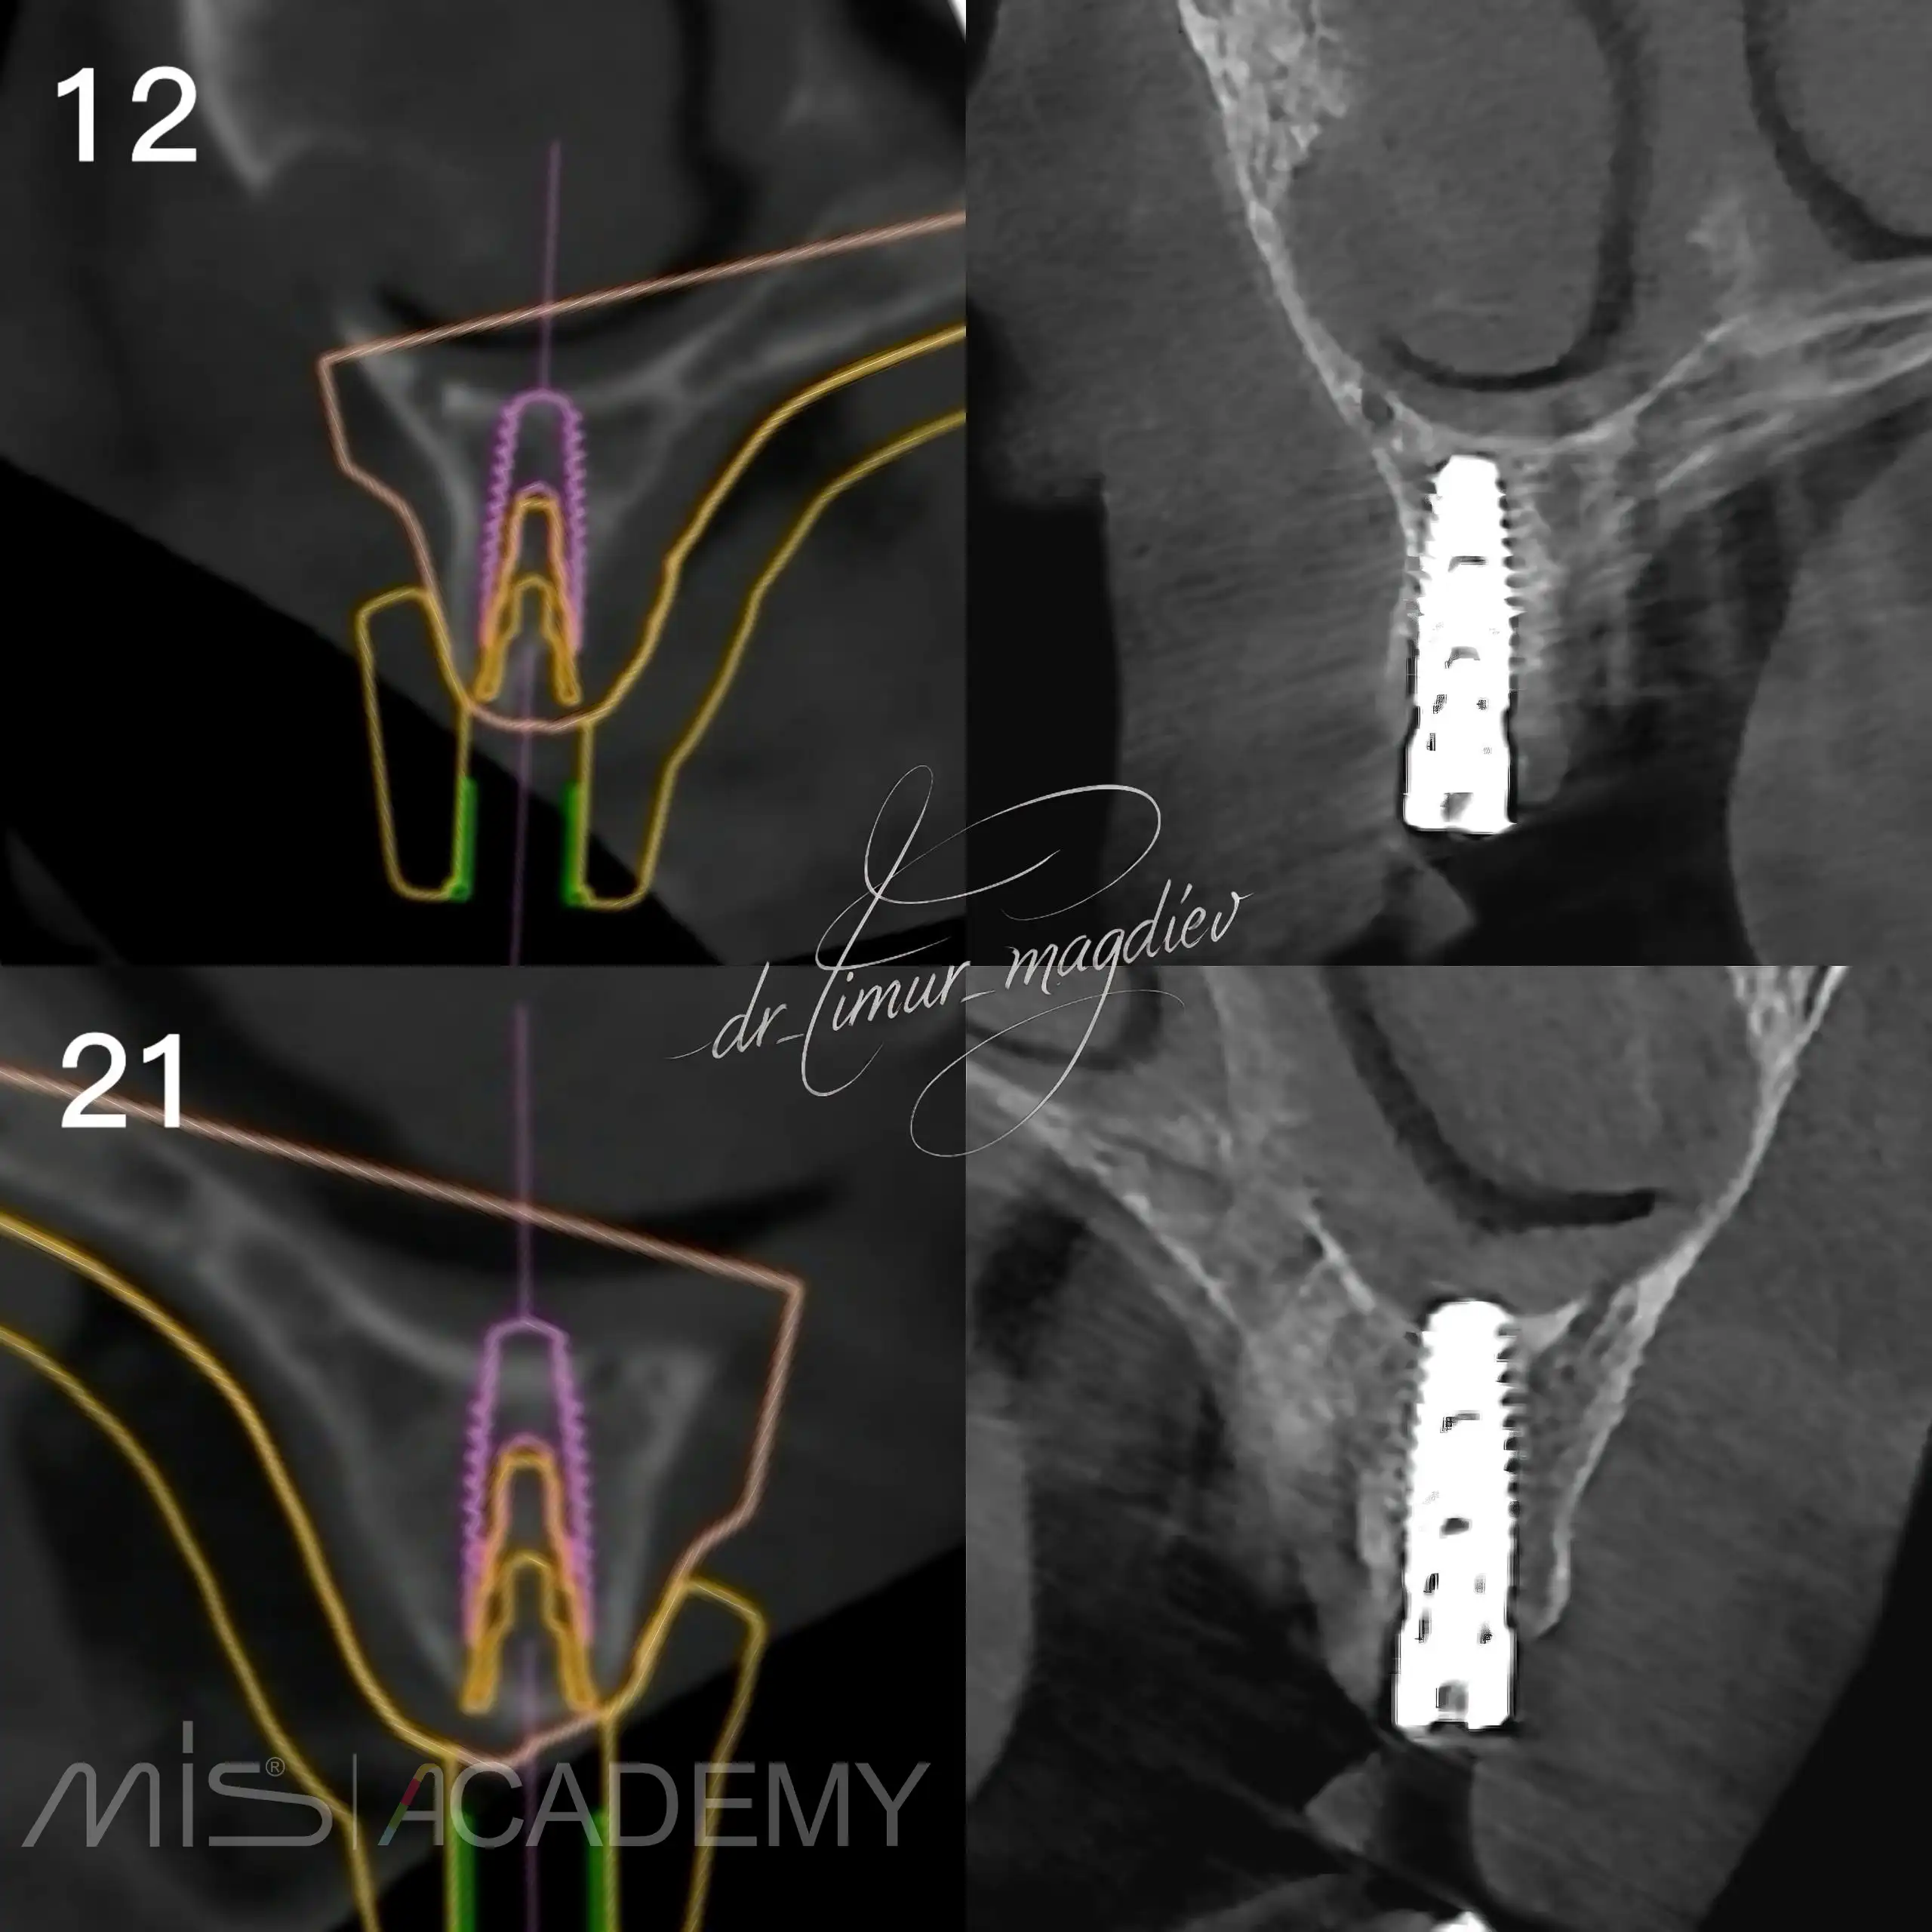

Комплексная реабилитация пациента; в полном навигационном протоколе:

— Установлены имплантаты MIS C1 + Connect абатменты.